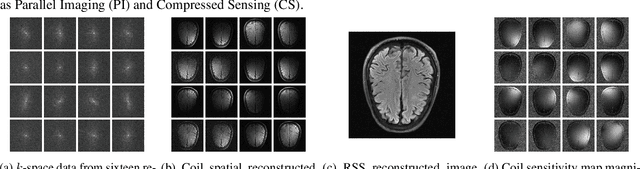

Figure 1 for Deep MRI Reconstruction with Radial Subsampling

Figure 2 for Deep MRI Reconstruction with Radial Subsampling

Figure 3 for Deep MRI Reconstruction with Radial Subsampling

Figure 4 for Deep MRI Reconstruction with Radial Subsampling